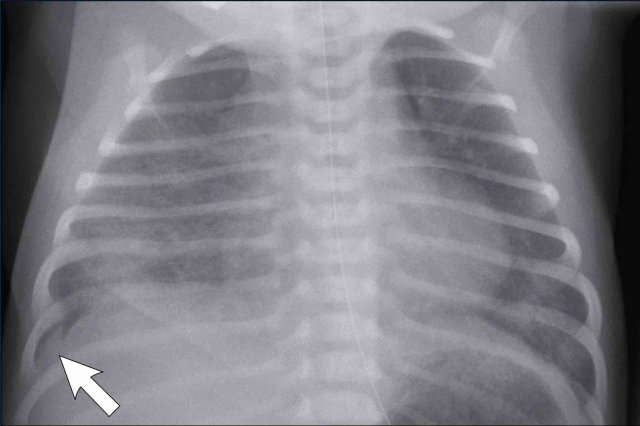

Full term infant, 2 hours after elective caesarean section with some respiratory distress.

Image

• Mild hyperinflation

• Subtle interstitial linings on both sides

• Some pleural fluid on the right side (arrow).

• Skin fold on the right side

After supportive therapy the respiratory distress disappeared the next day.